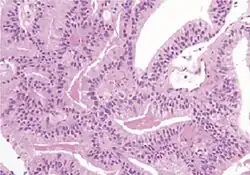

Ductal adenocarcinoma | 3% to 12.7%[8][notes 1] |

|

||||